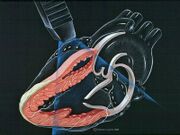

| 15:04, 4 August 2007 | Echo heart parasternal long axis small.jpg (file) |  |

24 KB | April | 1 | |